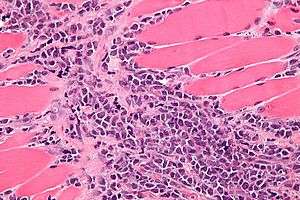

| Micrograph of a myeloid sarcoma within muscle. H&E stain. | |